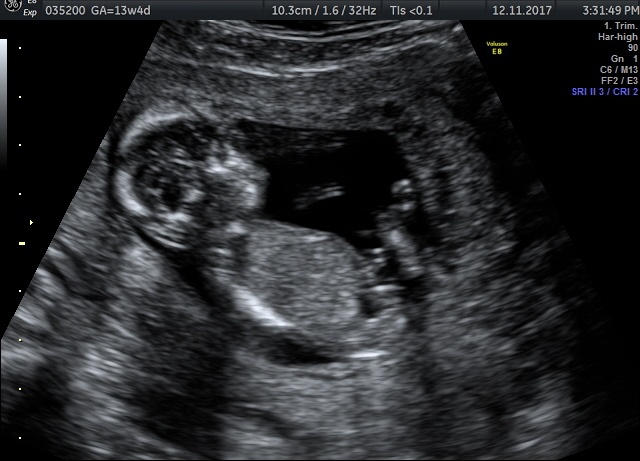

Please check my 13th week nt scan images and kindly tell the gender of my babyAttachment 38200